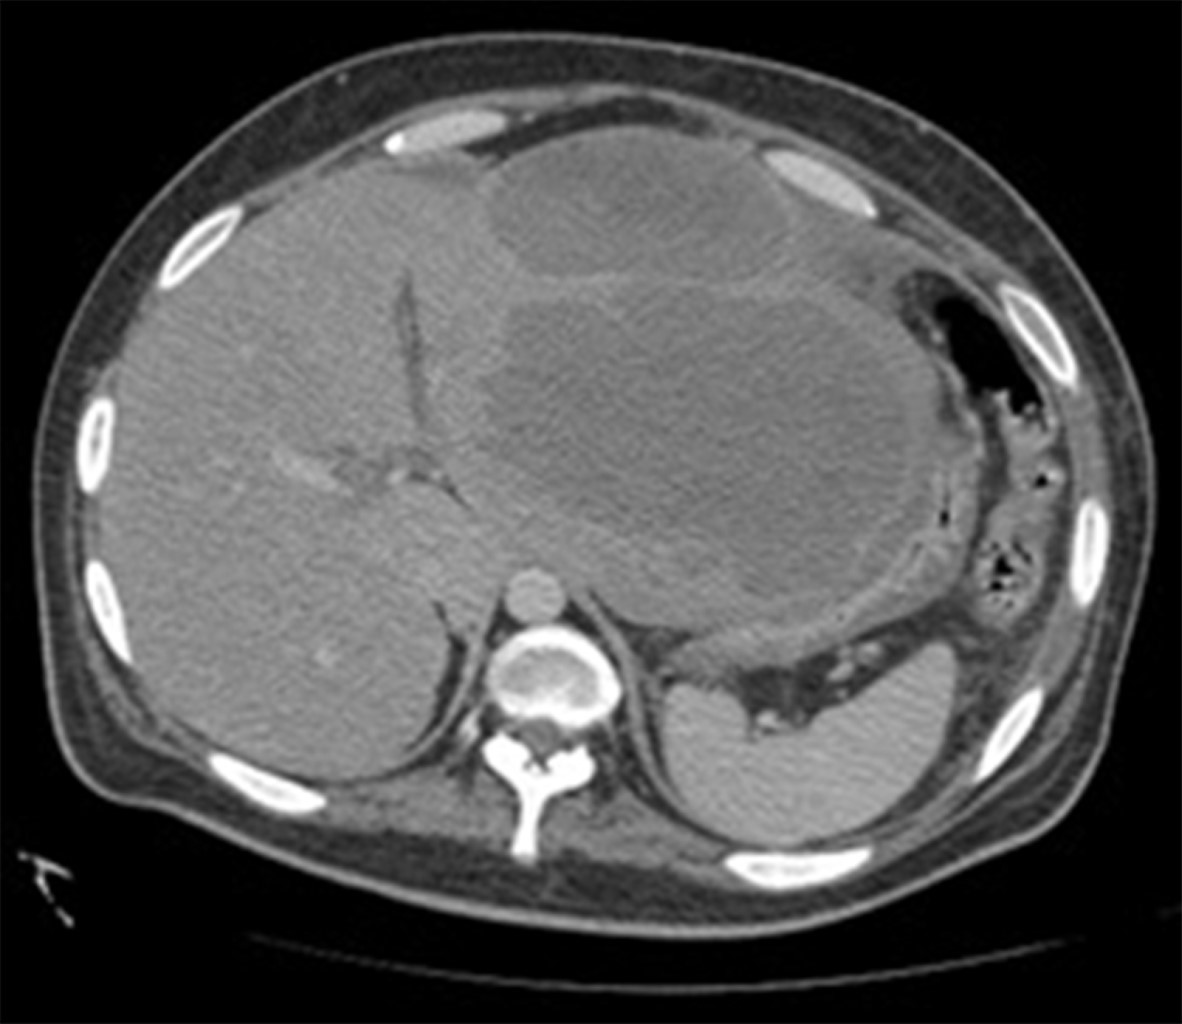

Se realizó una radiografía anteroposterior (AP) de tórax, en la cual se visualizó un derrame pleural izquierdo que cubría más de 50%. La tomografía computarizada mostró una importante cantidad de líquido en el espacio pleural izquierdo que condicionó una atelectasia pasiva del lóbulo inferior (Figura 1); el hígado se encontró con densidad heterogénea con incremento del lóbulo hepático izquierdo secundario a la presencia de una lesión heterogénea hipodensa con bordes lobulados, que muestra un reforzamiento periférico y de algunos septos internos, la cual abarca los segmentos II, III, IVa y IVb midiendo aproximadamente 20 × 14.5 × 12.5 cm (Figura 2), condicionando desplazamiento posterior y compresión del estómago y del páncreas y desplazamiento caudal de las asas intestinales (Figuras 3 y 4). En el polo inferior del lóbulo hepático derecho adyacente al segmento IV se identifica una lesión de aspecto quístico homogéneo con reforzamiento periférico tras la administración de contraste intravenoso, midiendo en sus ejes mayores 25 × 27 × 13 cm. Como manejo inicial se le colocó una sonda Foley y sonda nasogástrica presentando gasto de características gástricas (30 ml). Se colocó un catéter central, verificado por radiografía. Se solicitaron estudios de imagen. Se le indicó ayuno, se inició fluidoterapia, antibioticoterapia con ceftriaxona y metronidazol, manejo del dolor, control glucémico y protector gástrico. Al visualizar la imagen del derrame pleural izquierdo, se decide realizar una toracocentesis, obteniendo exudado espeso de aspecto "chocolatoso". Al momento de contar con la tomografía se inicia tratamiento quirúrgico urgente.

Figura 1